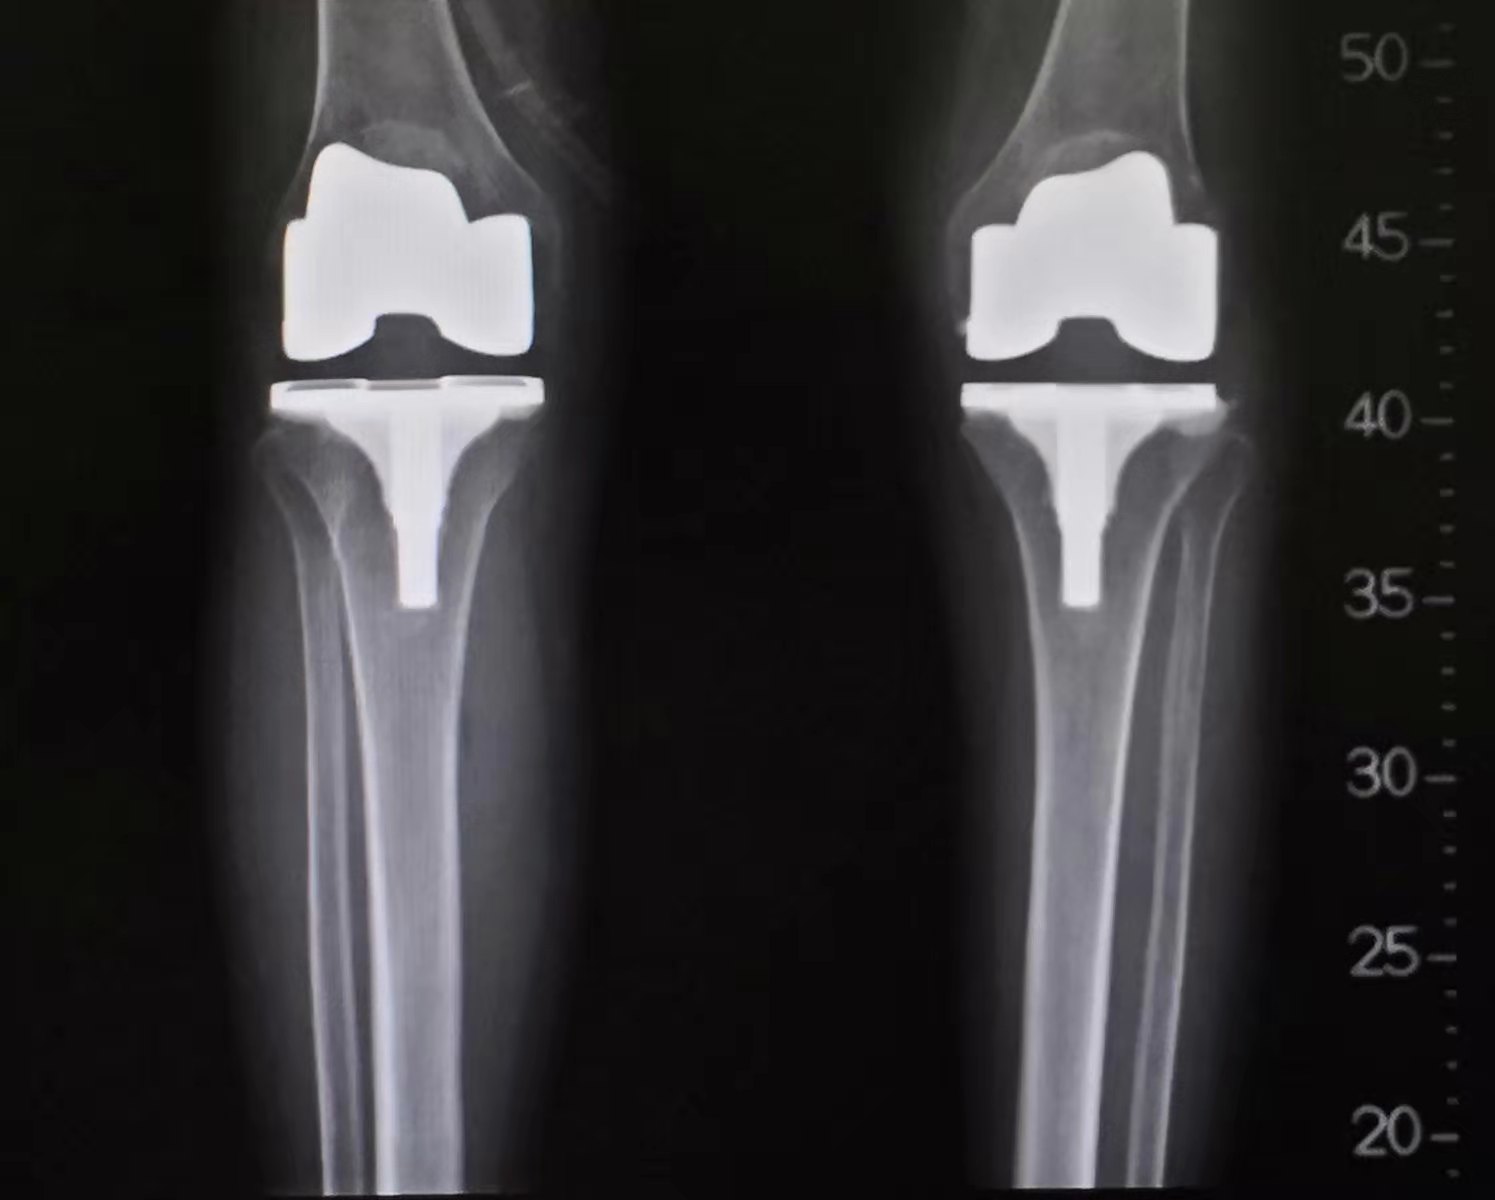

双侧TKA术后的正位片提示膝关节畸形得到纠正